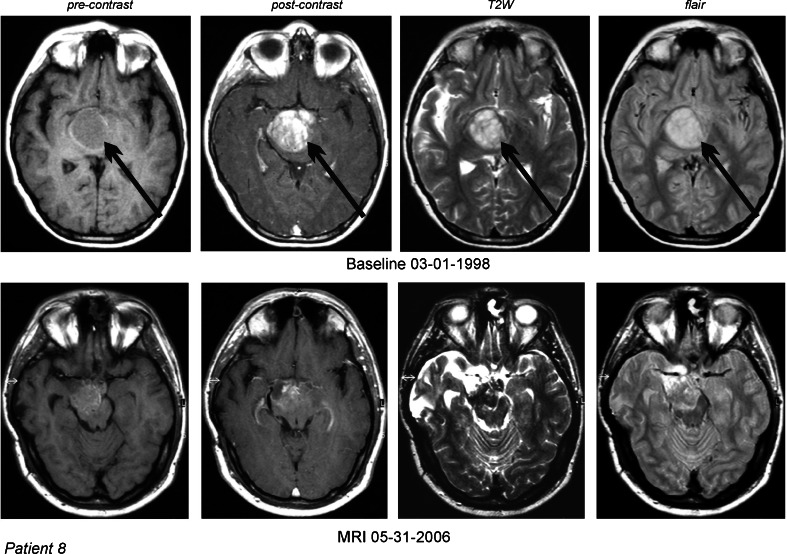

In the group of 17 RPDIPG patients, there were five cases of OR (29.5 %): one CR (6 %) and 4 PR (23.5 %). An additional group of two patients (11.8 %) had stabilization of their disease, eight patients (47 %) developed progressive disease, and two cases (12 %) were nonevaluable (NE). Figures 2 and 3 illustrate the response to treatment with ANP in two patients.

Fig. 2.

DIPG in a 10-year-old male (case 8) which recurred two times after partial surgical resection. MRI of the head: 1—T1 nonenhanced, 2—contrast-enhanced, 3—T2W, and 4—FLAIR images. PR was documented by the MRI and CR was established by the normalization of the follow-up PET scans. Arrows indicate tumors

| 8 | University/February 1, 1993 | PA | University Hospital/January 28, 1993 | DIPG | 2S | External Radiology, CRR/March 1, 1998 | Recurrence | 72 | External Radiology, CRR/January 16, 1999 and May 6, 2003 | PR, CR | Decreased >50 % | Decreased | Neg |